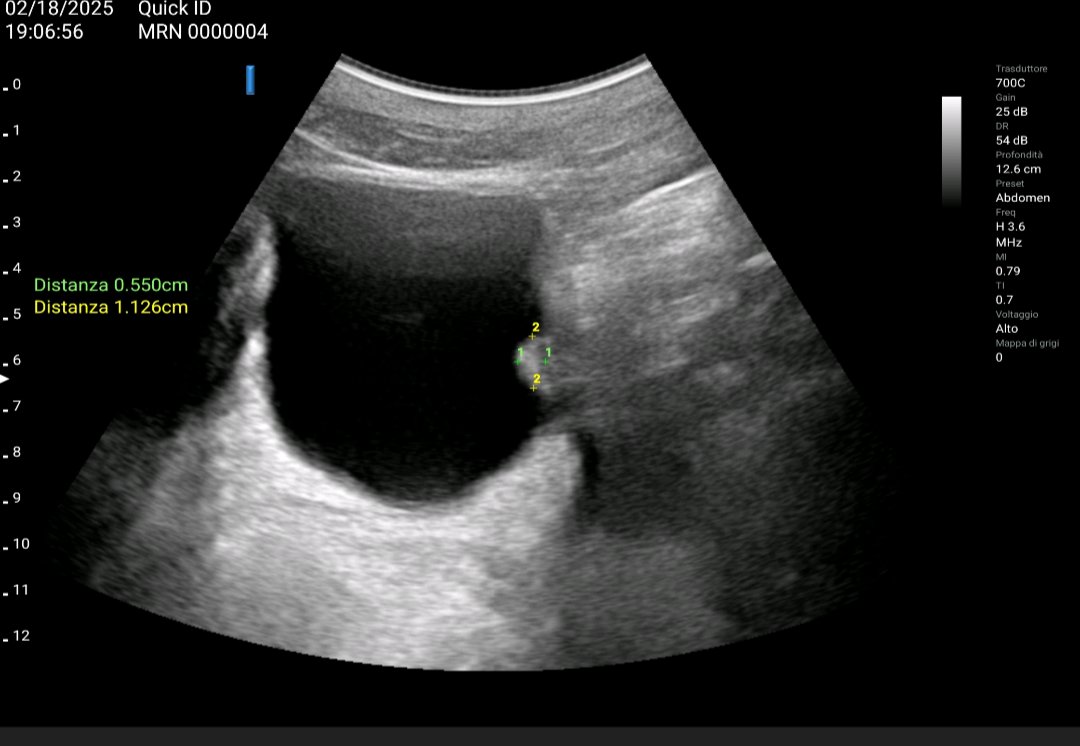

Varón 62a con cólico renal Izdo+ hematuria #ecografiaclinica permite imagen comparativa renal con ectasia de vía, vemos causa en unión uretero vesical -> litiasis con centelleo. Joaquín Martínez NephroPOCUS ABCDEcografía Pierpaolo Di Nicolò Dr. Miguel Molina - Ecografia Clínica - POCUS Jorge Zegarra ecoap EcosemFYC GRECOCAP